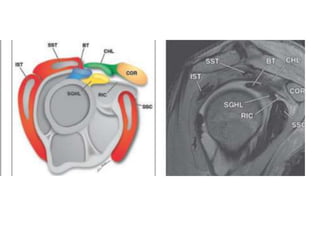

The rotator interval

• The superficial roof of the rotator interval is

the coracohumeral (CH) ligament and the floor

of the interval is the superior glenohumeral

ligament (SGHL).

The rotator interval •The superficial roof of the rotator interval is the coracohumeral (CH) ligament and the floor of the interval is the superior glenohumeral ligament (SGHL). • suspensory structure for the humeral head